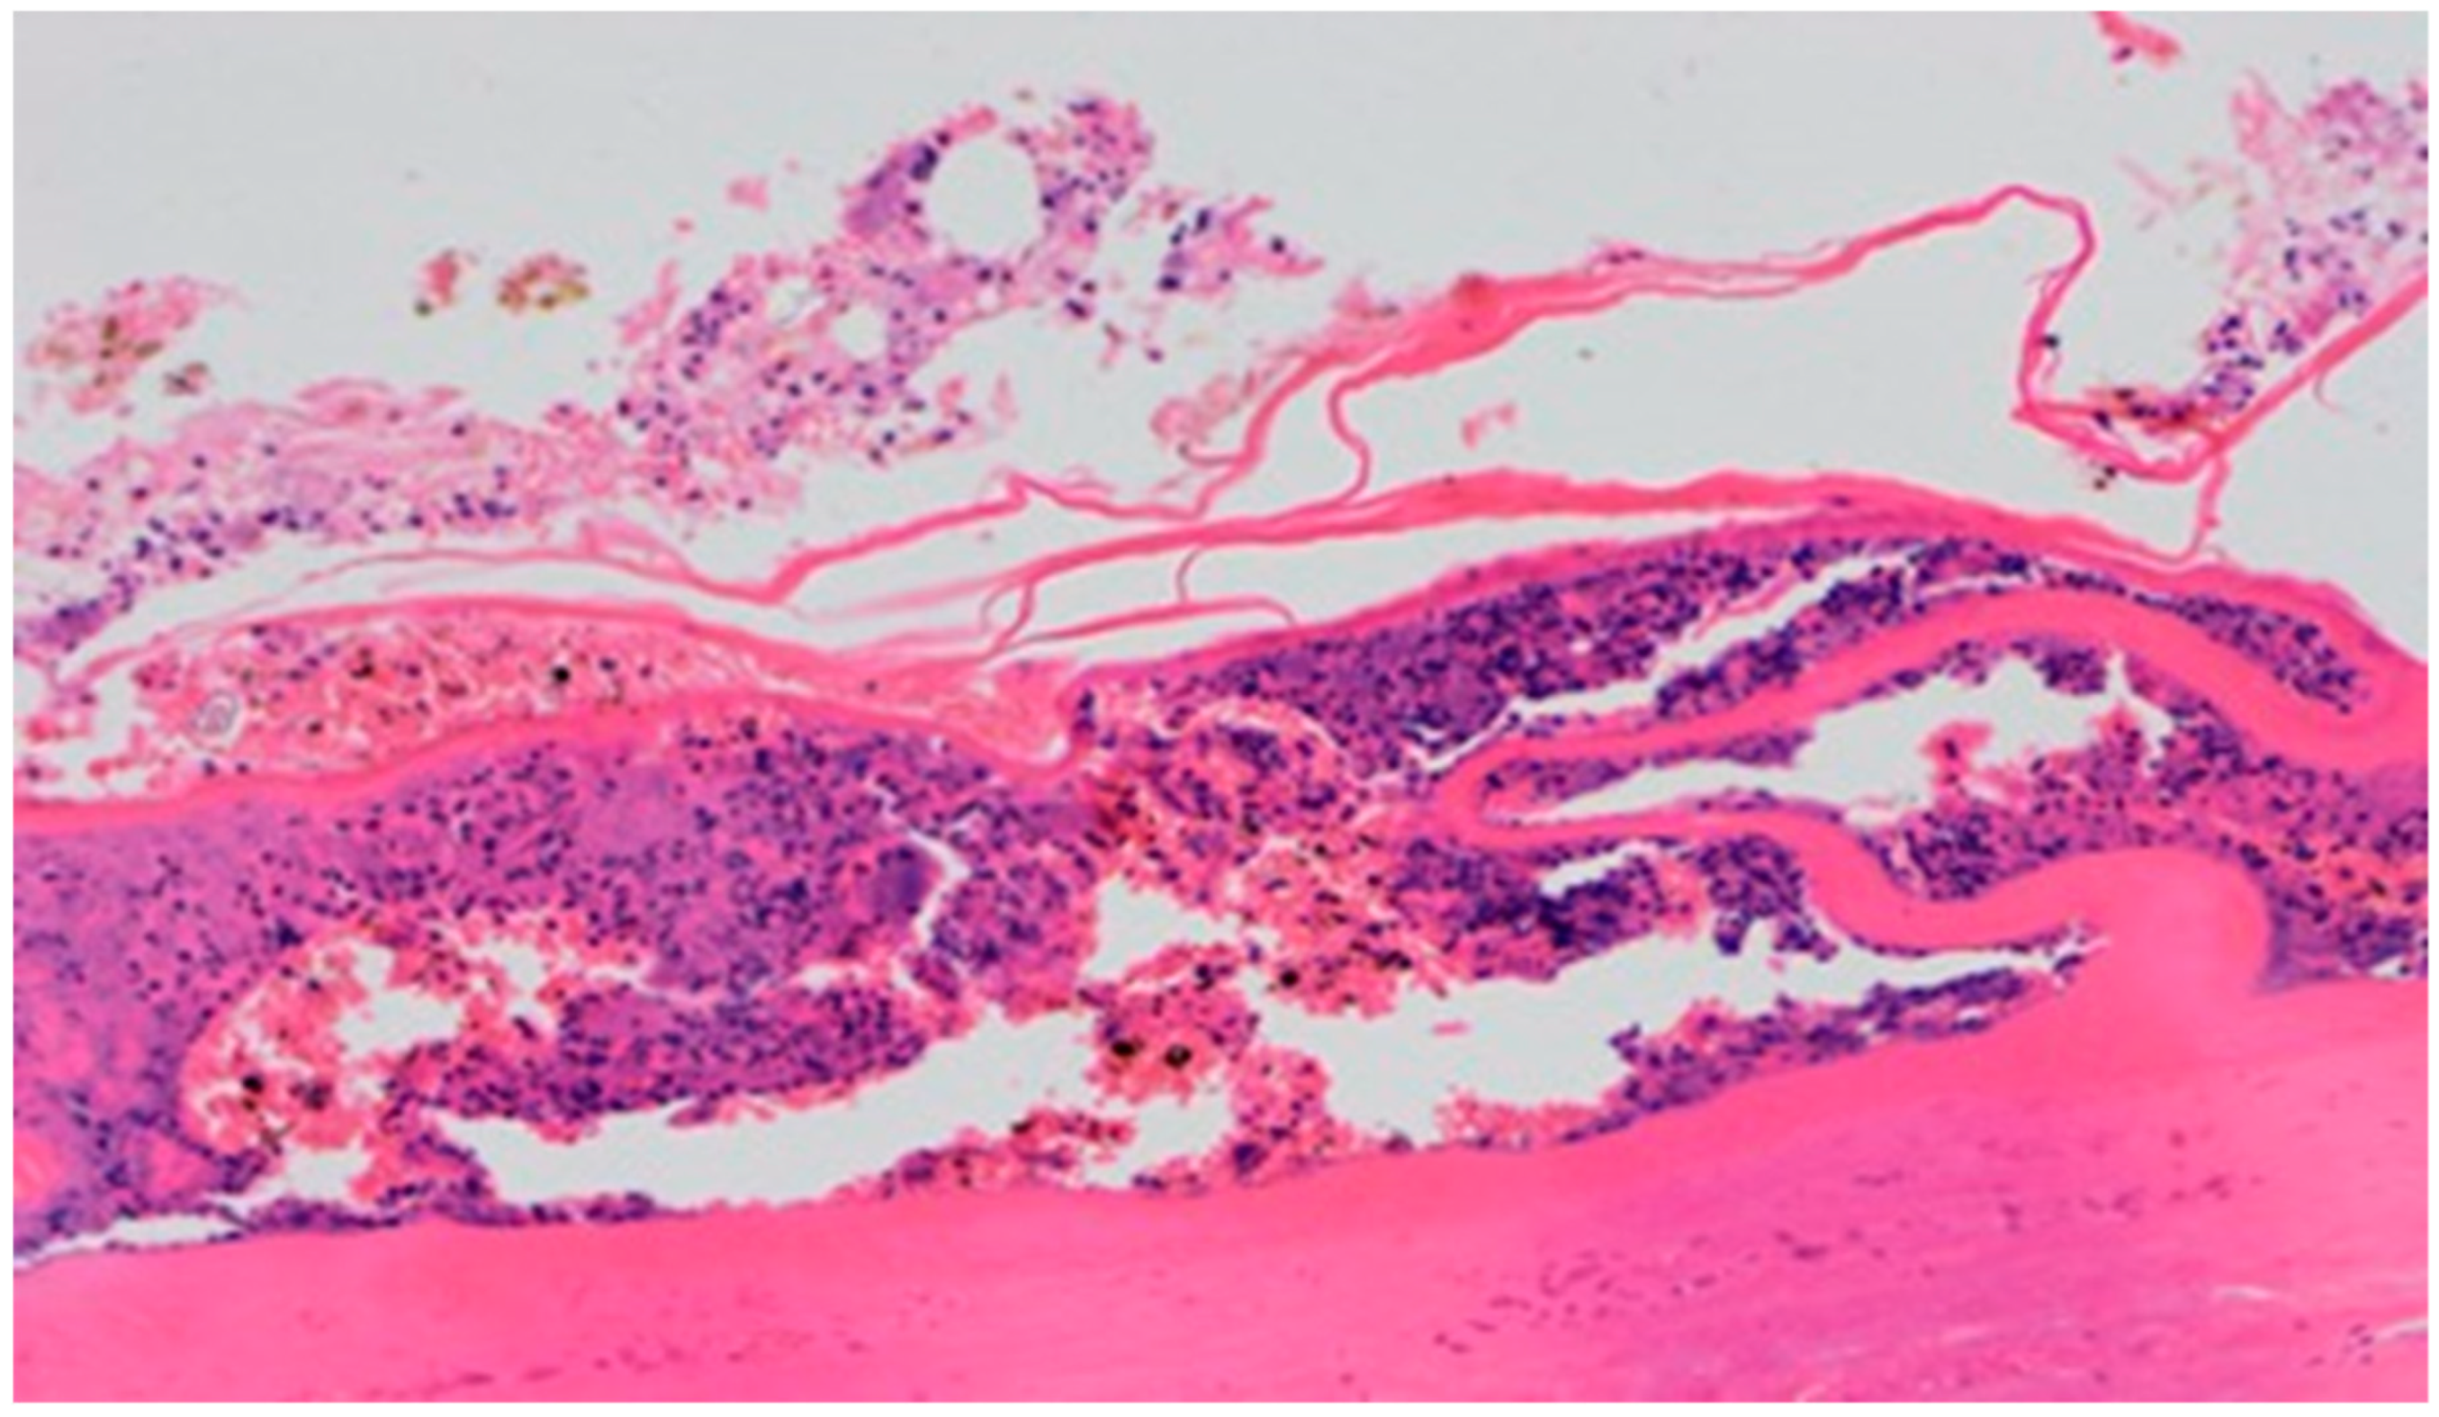

On day 5 of the experiment, slight differences in the wound healing process were observed. Inflammation was present in all wounds and the surrounding tissues, however, with a different intensity, type and depth of infiltration. In group D1, treated with the 1% propolis ointment, there was a moderately dense granulocytic infiltration reaching the dermis. Wounds in group D2, treated with the 1% nanosilver ointment, were characterized by a granulocytic infiltration with a low density and depth of infiltration reaching the dermis. In wounds treated with a mixture of 1% propolis and 1% nanosilver, there was a large granulocytic inflammatory infiltration reaching the depth of the adipose tissue. Wounds treated with sulfathiazole were characterized by a small, mixed infiltration reaching the dermis. On day 5 of the treatment, all wounds from the experimental and control groups did not show any epidermization features. Superficial necrosis was low in the experimental groups and a high degree of necrosis was observed in the sulfathiazole-treated control group. The histopathological findings from day 5 are presented in Table 8 and Figure 13 and Figure 14.

Figure 13. Granulocytic inflammatory infiltration on the border of the dermis and subcutaneous tissue (100×, H-E), in the wound treated with the ointment with 1% propolis and 1% nanosilver, on day 5.

Figure 14. Necrosis, with granulocytic inflammatory infiltration (100×, H-E), in the wound treated with sulfathiazole, on day 5.